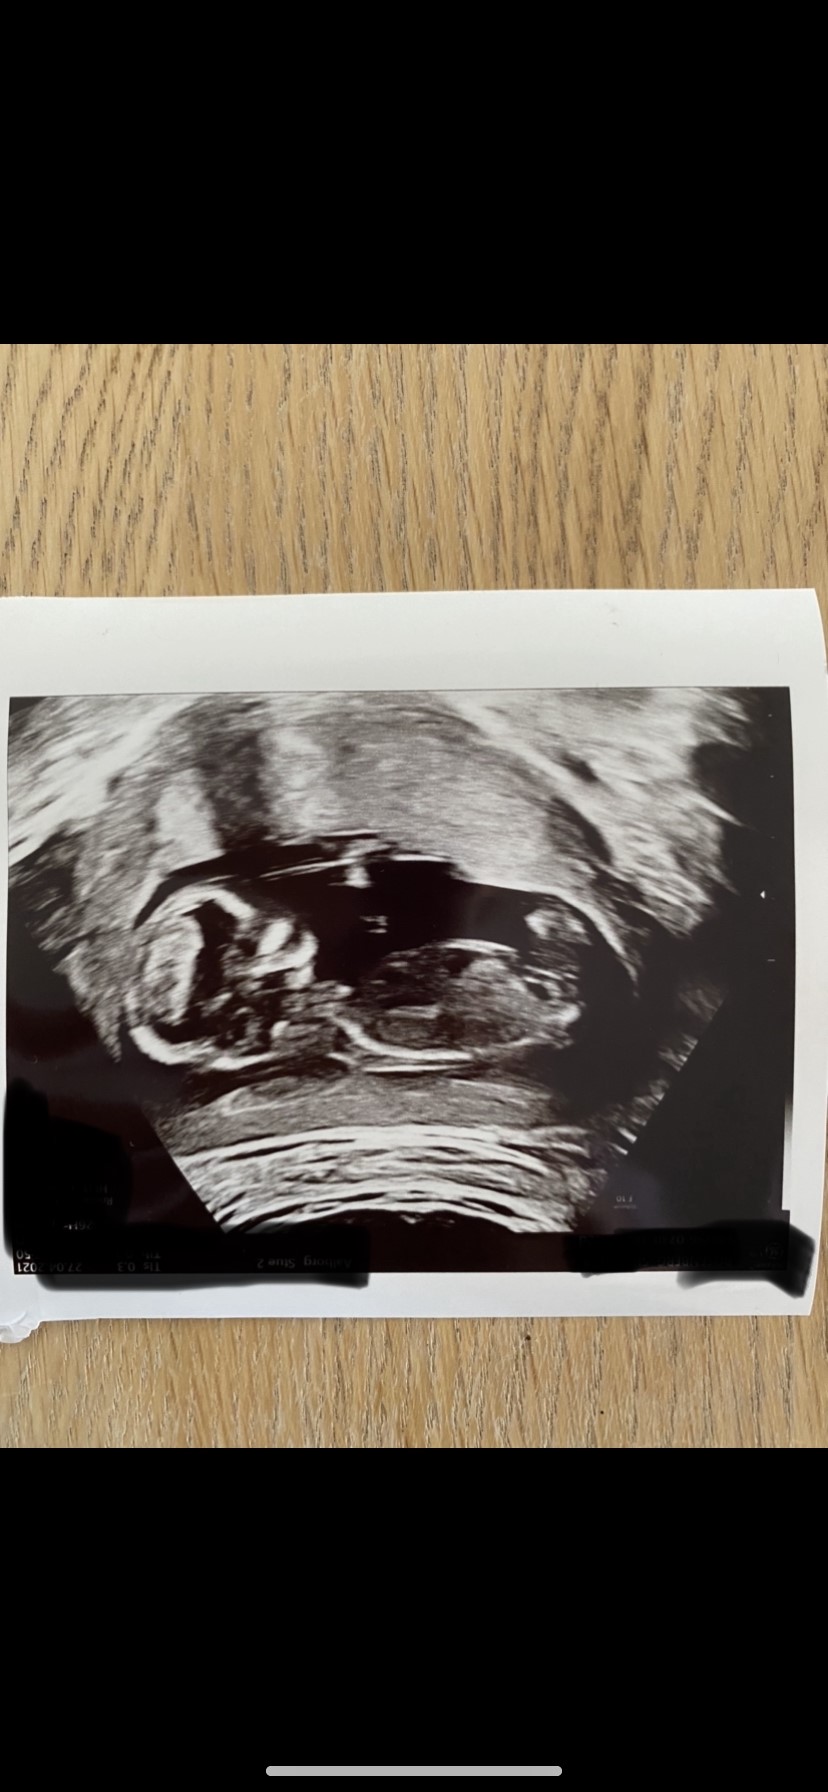

Vil i gætte hvad der ligger i min mave?

Vedhæftede fotos (klik for at se i fuld størrelse)

Jeg vil gerne komme med et forsigtigt gæt på pige ud fra billede nr 2

Tænker også umiddelbart pige

Jeg gætter også på en pige